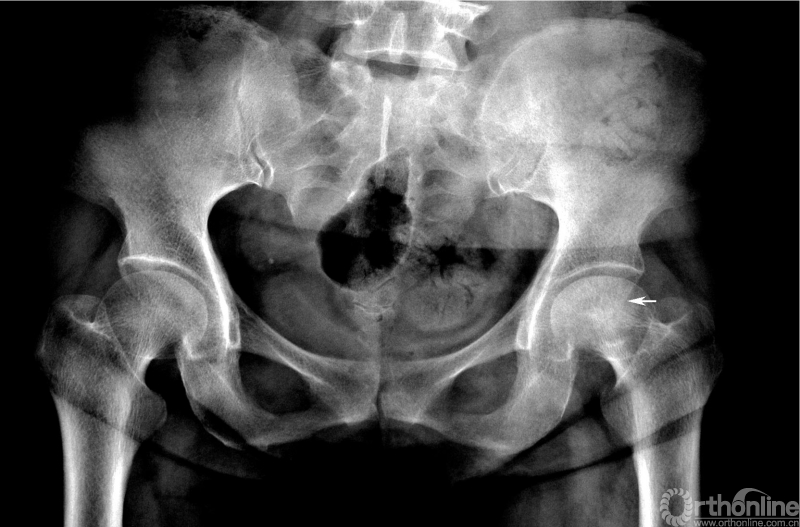

成人股骨头缺血坏死(早期)

左股骨头内斑片状硬化区,边界模糊,股骨头外形和关节间隙正常

股骨头内出现散在的斑片状或条带状硬化区,边界模糊,股骨头外形和关节间隙正常。